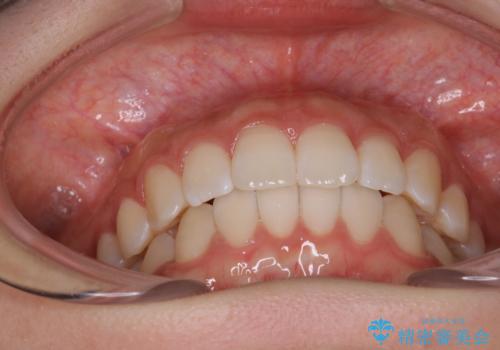

前歯のがたつきをインビザラインで目立たない矯正

- 上下の前歯のがたつきを主訴に来院されました。

マウスピースでの矯正を希望されたので、インビザラインで矯正治療を行うこととしました。

インビザラインではシュミレーションによりどのように歯が動くかを確認して矯正することができるので、患者様も安心して矯正をすることができました。